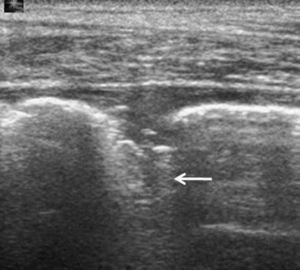

Costillas y esternónLa ecografía es útil en la detección de fracturas costales y esternón, y es más sensible que la radiografía convencional7,75. La aparición del fenómeno de la chimenea (chimney phenomenon) permite diagnosticar las fracturas en que no existe desplazamiento de los bordes. Este fenómeno consiste en la presencia de reverberaciones posteriores en el punto de fractura. La ecografía permite, además, diagnosticar complicaciones asociadas, ya sean leves, como los hematomas perióseos y desplazamiento de fragmentos76, o complejas, como hemotórax y neumotórax.